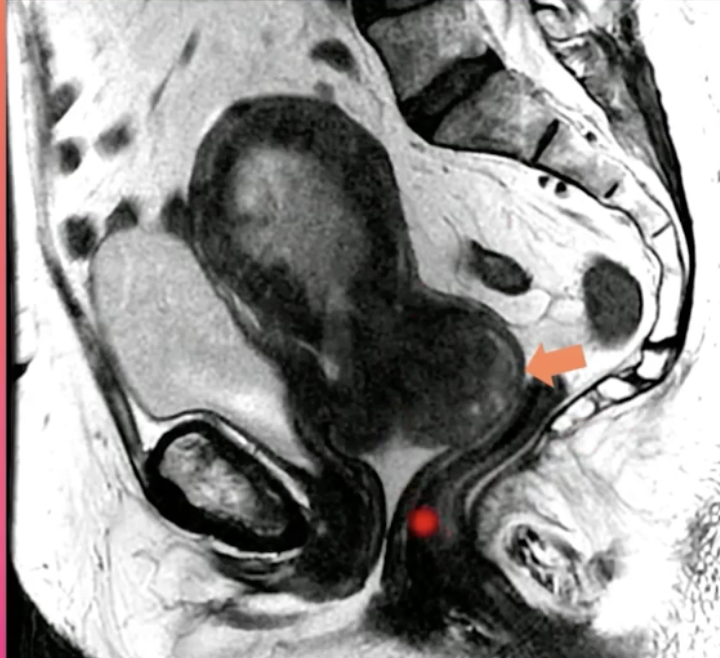

Qual o diagnóstico?

A

CA de Endométrio